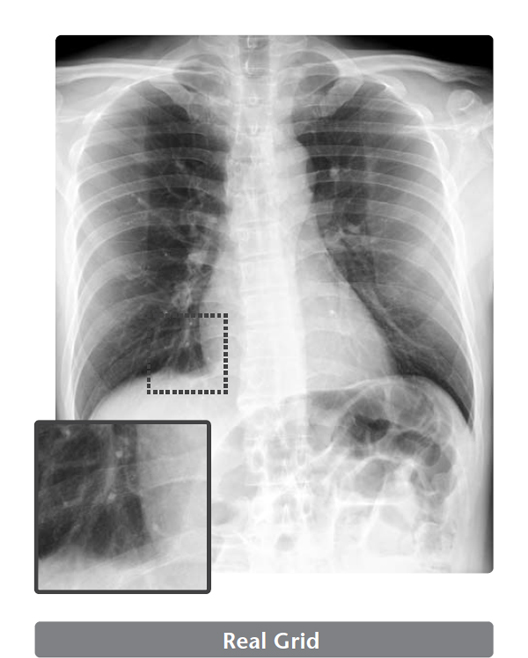

Image processing that remove the scatter X-rays from the digital radiography created without a physical grid.

Virtual Grid is an image processing software that corrects for the effects of scatter X-rays that otherwise reduce image contrast and clarity.

Without the need for physical grid, this software quickly predicts and then corrects for the effects of scatter X-rays, creating an improved image quality.

High quality images can be obtained under low dose conditions, thus reducing the amount of radiation does the patient receives*4.

- *4 In CD-RAD phantom evaluations performed by FUJIFILM, when compared with images acquired with an 8:1 grid, comparable non-grid images processed with Virtual Grid software yielded a 50% reduction in dose.

Virtual Grid allows setting of the grid ratio, number of grid lines and interspace material, and examinations using the appropriate grid conditions.

Just as for a physical grid, different Virtual Grid settings can be used, best suited for the different regions and exposure conditions.

Of course, as it is a virtually created grid, the grid type can be changed after an exposure